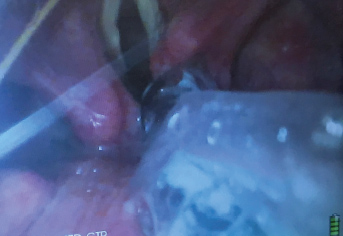

When the trachea is extremely tortuous and it has been impossible to slide a standard ETT over the FIS into the trachea, a spirally reinforced or "armored" ETT can be used. This type of ETT will follow the FIS more easily because it has less internal rigidity and therefore conforms more readily to unusual tortuous airway anatomy. The Parker flex tip endotracheal tube has also been shown to pass more easily over a fiberscope than a conventional ETT [37]. The ETT that is provided with the intubating LMA is a soft wire-reinforced silicon tube and its tip conforms readily to airway anatomy and is also excellent at sliding easily over a flexible bronchoscope (Figure 3, Figure 4 and Figure 5) [38].

Figure 3: The vocal cords are visualized with the video-laryngoscope (VL) while the flexible intubation scope (FIS) is used to steer the endotracheal tube (ETT) into the trachea.

Figure 4: Video-laryngoscope (VL) view of a flexible intubation scope (FIS) passing over the arytenoids. The FIS is ante-flexed by pushing the thumb down.

Figure 5: Video-laryngoscope (VL) view of the flexible intubation scope (FIS) having passed the vocal cords. The FIS is retroflexed by pushing the thumb up.